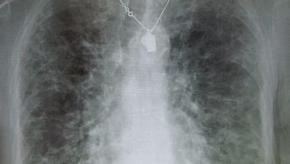

Read ArticleNew Drugs, New Hope for Pulmonary Fibrosis

The Wall Street Journal reports that new drug development offers hope for people with idiopathic pulmonary fibrosis, a rare, progressive fibrosing lung disorder that affects nearly 200,000 Americans, mostly middle-aged and older adults.

Read ArticleHigh False Negative Rate with PFTs in Scleroderma

Researchers in Zurich studed 102 systemic sclerosis with serial PFTs and high-resolution computed tomography of the chest (HRCT). They found significant interstitial lung disease (ILD) by HRCT in 63 percent.